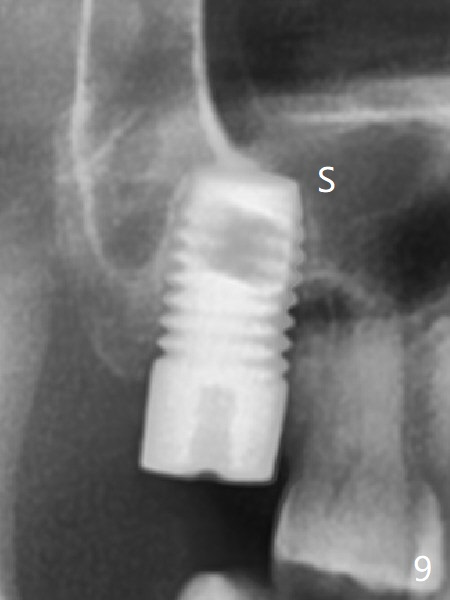

Preop exam shows that the tooth #2 has split into the buccal (Fig.1 B) and palatal (P) halves. When the tooth is extracted (Fig.2), there is a large piece of granulation tissue between these halves. The socket is large with sinus floor having pointed perforation. The latter is enlarged with rounded tapered Tatum osteotomy 2-4 mm, followed by tapered and then rounded taps. A 6.8x14 mm rounded tap has barely enough stability (Fig.3). Following placement of 2 PRF plug and 2 PRF membranes and allograft/Osteogen, a 8x17 mm cylindrical implant is placed with 60 Ncm (implant machine reading), however the implant is unstable (Fig.4). More graft is placed around the implant. With placement of 6x3 mm abutment, an immediate provisional is fabricated to close the socket. There is nasal discharge for a few days postop. PAs taken nearly 6 months postop show no bone loss (Fig.5,6). The definitive crown is cemented with access hole; there is no residual cement (Fig.7 (9 months postop)). The crown is loose 1 month post cementation (last March, Fig.8 with periimplant space (*)). The unipost was not cemented due to gag reflex. He refuses treatment immediately because of the allergy season. When he returns, spray a topical to his throat. Following crown removal, implant is found to have mobility. Panoramic X-ray (Fig.9) and CT (Fig.10,11) show fibrointegration (space) and implant intrusion into the sinus (S) without bone formation. After implant removal, the sinus floor and membrane are found to have been perforated. Osteogen plug is placed, followed by Vanilla/Osteogen (Fig.12 *) and Osteogen plug. It appears that an immediate implant is contraindicated when there is severe infection (Fig.2) with sinus floor perforation. In this case, the bone density at the upper 2nd molar is low (Fig.10 distopalatal view of 3-D image). Bone expansion and condensation is needed for implantation. Progressive loading is also necessity prior to impression.